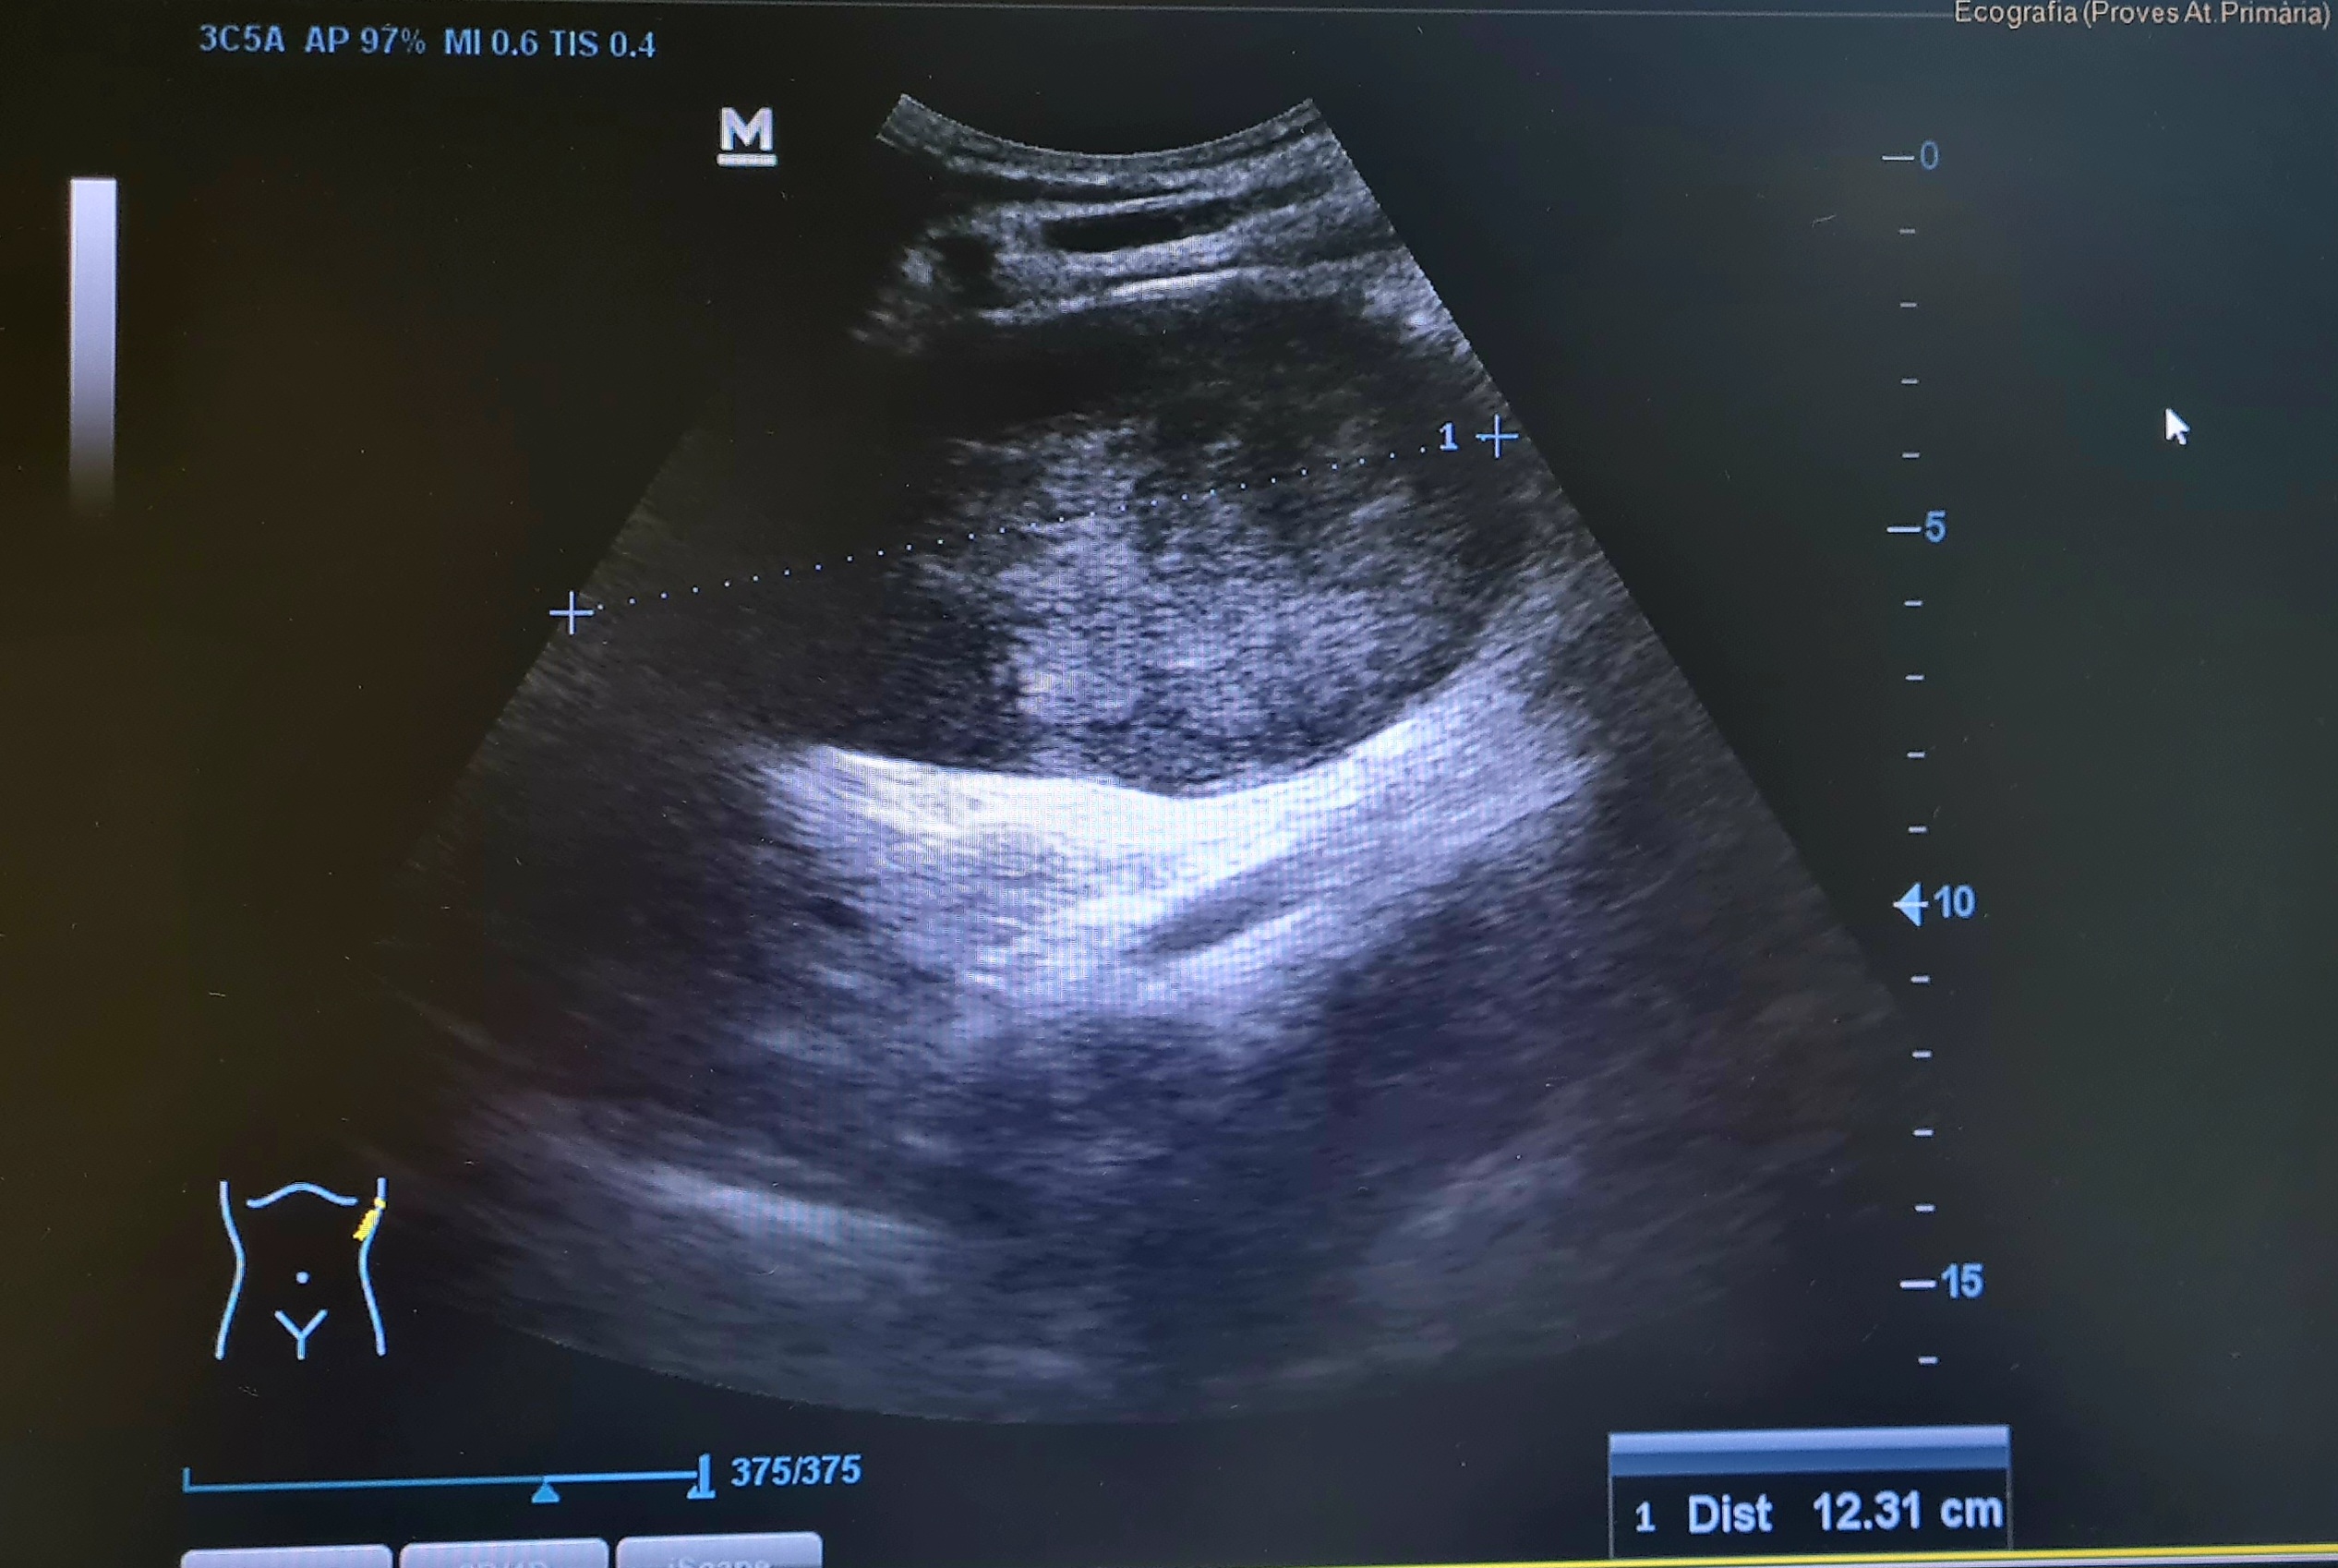

Con el diagnóstico de cólico persistente se practica una ecografía a pie de cama para descartar obstrucción, que muestra una gran masa en hipocondrio Izquierdo, que parece depender de bazo.

Se solicita TC abdominal urgente que informa (día 74): Aumento de tamaño del bazo a expensas de voluminosa lesión nodular sólida y heterogénea con centro hipodenso, siendo de unos diámetros máximos aproximados de 8x10,5x13,5 cm, que se asocia a cambios inflamatorios en la grasa periesplénica inferior. Como primera opción diagnóstica sugiere proceso linfoproliferativo.